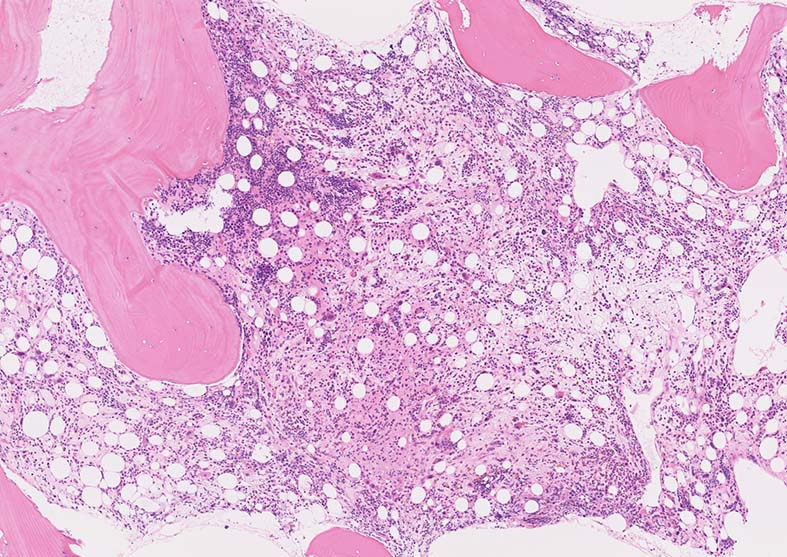

骨髄生検組織

M7_biopsyMG.jpg

1. 芽球増生の著明な髄様組織をしめすmegakaryoblastic leukaemia

2. 芽球の増殖が乏しく, myelofibrosisのみがめだつ2つのタイプがある。

骨髄生検組織: 骨梁は軽度に肥厚している. 明瞭な硬化像はない. 鍍銀染色でびまん性に線維増生が認められる.

Bone marrow biopsy HE染色: A: 脂肪細胞は減少しているが線維化により造血細胞は疎になっている. B:小型Mgkが散在性に多数認められる.核は類円形, 小型低分葉の細胞が多く, 分離円形核をもつ異形成Mgkが出現している.

C:骨梁に沿って赤芽球が局在している. 通常は顆粒球系細胞が骨梁辺縁に局在する.

骨髄組織所見

正形成髄ないし過形成髄を呈する.

造血巣には, 巨核芽球と種々の成熟段階の異型巨核球が優位に増殖する. 両者の比率は症例によりさまざま.

小型巨核球が一様に増殖する症例では他のAML病型と形態的に区別ができないときがある.

巨核芽球とともに多数の成熟巨核球が増殖する症例もあるが, このときの成熟巨核球は一般に小型で, 低分葉核をもち異形成がめだつ.

微小巨核球が孤在性にあるいは集簇して多数認められる場合もある. クロマチンに濃染する1-2個の成熟核をもち成熟巨核球にみられる淡好酸性細胞質をわずかに有する細胞として見られる. 組織切片で巨核球系と同定するにはCD42b, CD61などの免疫染色が必要になる.

骨髄系, 赤芽球系の幼若細胞や異型細胞が混在することがあるが数はすくない.

骨髄線維症をともなうことがAML-M7の重要な特徴であるが, 必発ではない. 髄様の病変の症例がある.

弾性線維増殖であることが多いが, ところどころに膠原線維の増生を伴うことがある. (鍍銀染色, EVG, Azan染色で評価する)